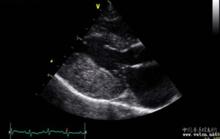

貓 心肌肥大英短和美短是比較常見的純種貓,大家也都覺得它們的身體很健康。事實上英美短也是有遺傳病症的(純種貓大多都有點什麼病)。 英美短的遺傳病並不可以小覷,這類貓咪最容易出現心血管類的遺傳病,尤其是公貓,最容易患上心肌上的疾病。這種疾病一旦發作就會有猝死的風險,因此主人們必須格外注意。

心肌肥大是英美短最常見的心肌類疾病,這種疾病初期沒有什麼明顯的症狀,一旦症狀明顯,就已經有了生命危險。主人們可以在貓咪遺傳病高發的年齡多多注意它們的身體,如果條件允許可以帶它們定期到寵物醫院檢查檢查身體。

英美短的遺傳病一般會在1-3歲時發作,所以在這個階段貓咪主人們要進行科學的餵養,以降低貓貓發生意外的幾率。